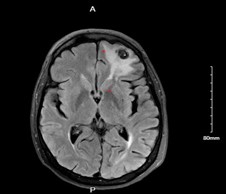

Clinical History: 66-year-old female with presents with seizures and progressive enlargement of anterior cranial fossa presumed meningioma with increased surrounding vasogenic edema approximately 4 years after Gamma Knife surgery.

Radiology: Extra axial lesion along the anterior inferior left frontal convexity, demonstrates some mild intrinsic T1 and T2 hyperintense signal, mostly T2/FLAIR hypointense with prominent susceptibility artifact. Moderate amount of T2/FLAIR hyperintense signal within the white matter of anterior and inferior left frontal lobe.